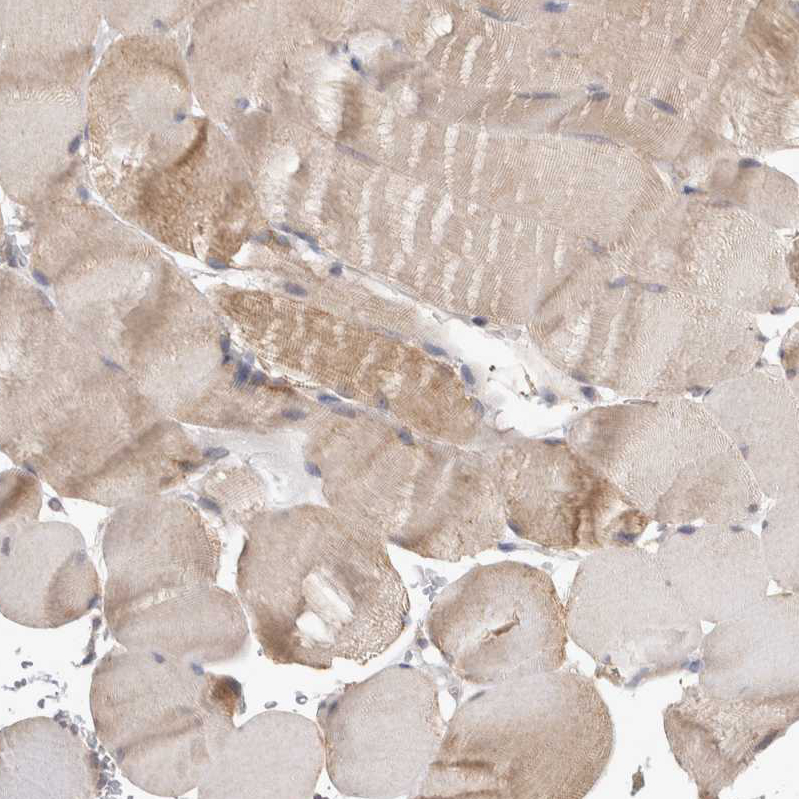

Immunohistochemical staining of human placenta shows moderate cytoplasmic positivity in trophoblastic cells.